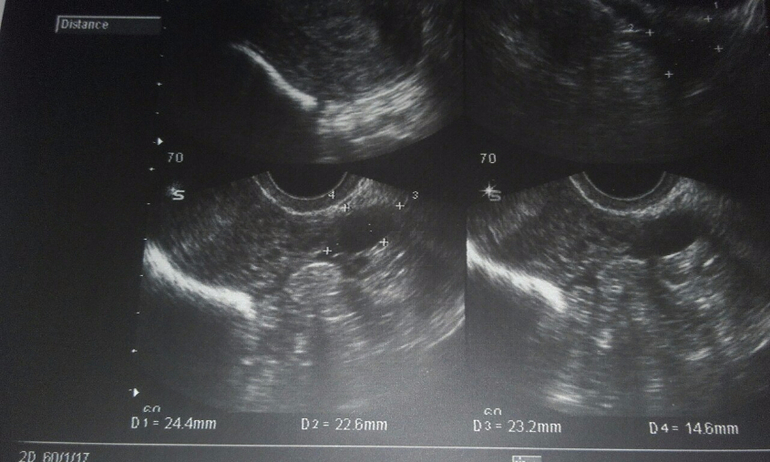

Да..Один ДФ лопнул..Она сказала еще один 23 мм уже..Я обалдела..Но..Она сказала что он может и не успеет..Так как М через неделю..Хотя..